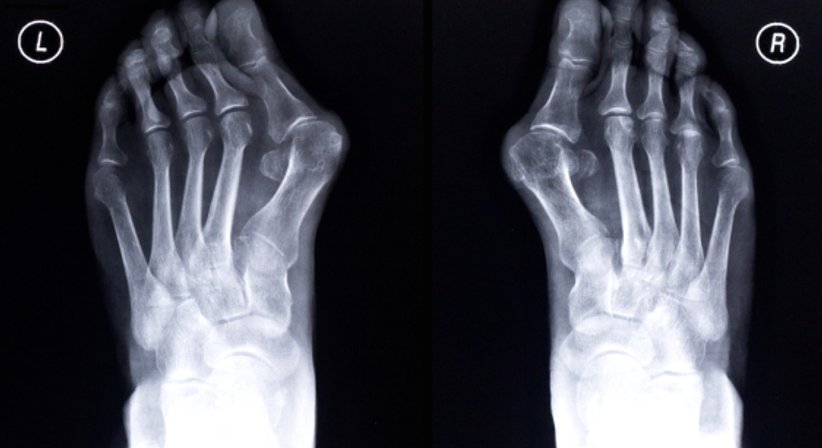

Beim Hallux valgus handelt es sich um eine Fehlstellung der Großzehe - die Großzehe verschiebt sich zur Fußaußenseite in Richtung der kleineren Zehen und verdrängt die anderen Zehen in manchen Fällen sogar von ihrer natürlichen Position. Durch die Fehlstellung beginnt sich der Ballenbereich am Innenfuß vorzuwölben und die für den Hallux valgus charakteristische Beule wird nach und nach deutlich sicht- und tastbar. Im weiteren Verlauf kommt es zu Schmerzen, da der vergrößerte Ballen gegen den Schuh drückt und das darunterliegende Gewebe einer dauerhaften Reizung ausgesetzt ist.